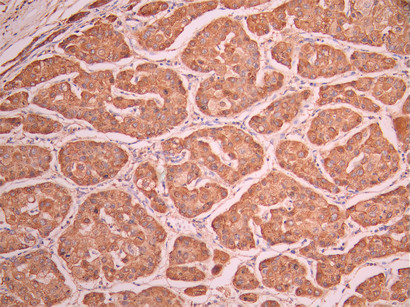

IHC image of CSB-RA048081A0HU diluted at 1:100 and staining in paraffin-embedded human liver cancer performed on a Leica BondTM system. After dewaxing and hydration, antigen retrieval was mediated by high pressure in a citrate buffer (pH 6.0). Section was blocked with 10% normal goat serum 30min at RT. Then primary antibody (1% BSA) was incubated at 4°C overnight. The primary is detected by a Goat anti-rabbit polymer IgG labeled by HRP and visualized using 0.05% DAB.